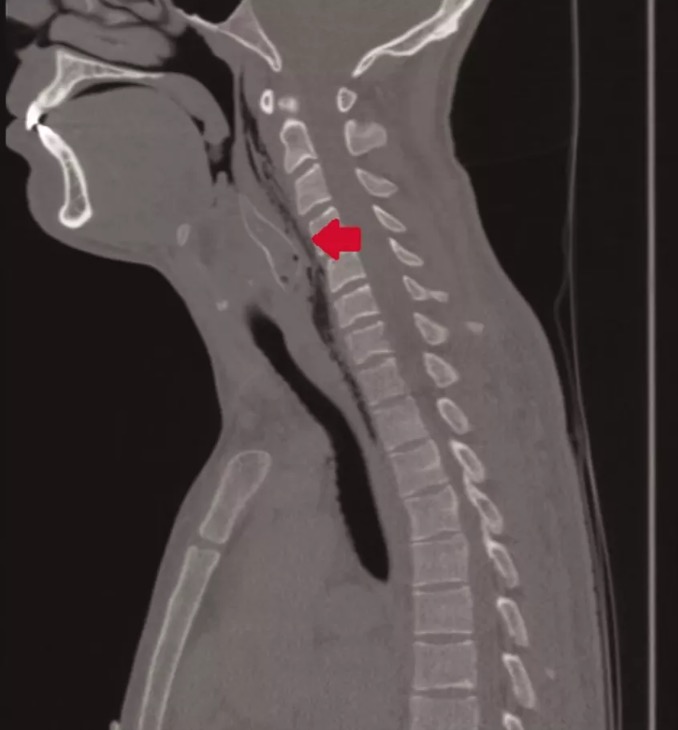

Ao chegar no hospital, médicos identificaram uma estrutura de espinha de peixe em sua garganta, isso porque o paciente havia engolido um peixe da espécie Corydoras aeneus, que tem poderosos mecanismos de defesa. Apesar de ter entre cinco e oito centímetros, quando ficam perturbados, os peixes deixam suas espinhas eretas e começam a soltar veneno.

O peixe havia morrido no esôfago do paciente, que precisou passar por uma cirurgia parar remover as espinhas do animal sem causar danos ao tecido da garganta. O procedimento foi realizado e o paciente não parece ter sofrido consequências do veneno do animal.